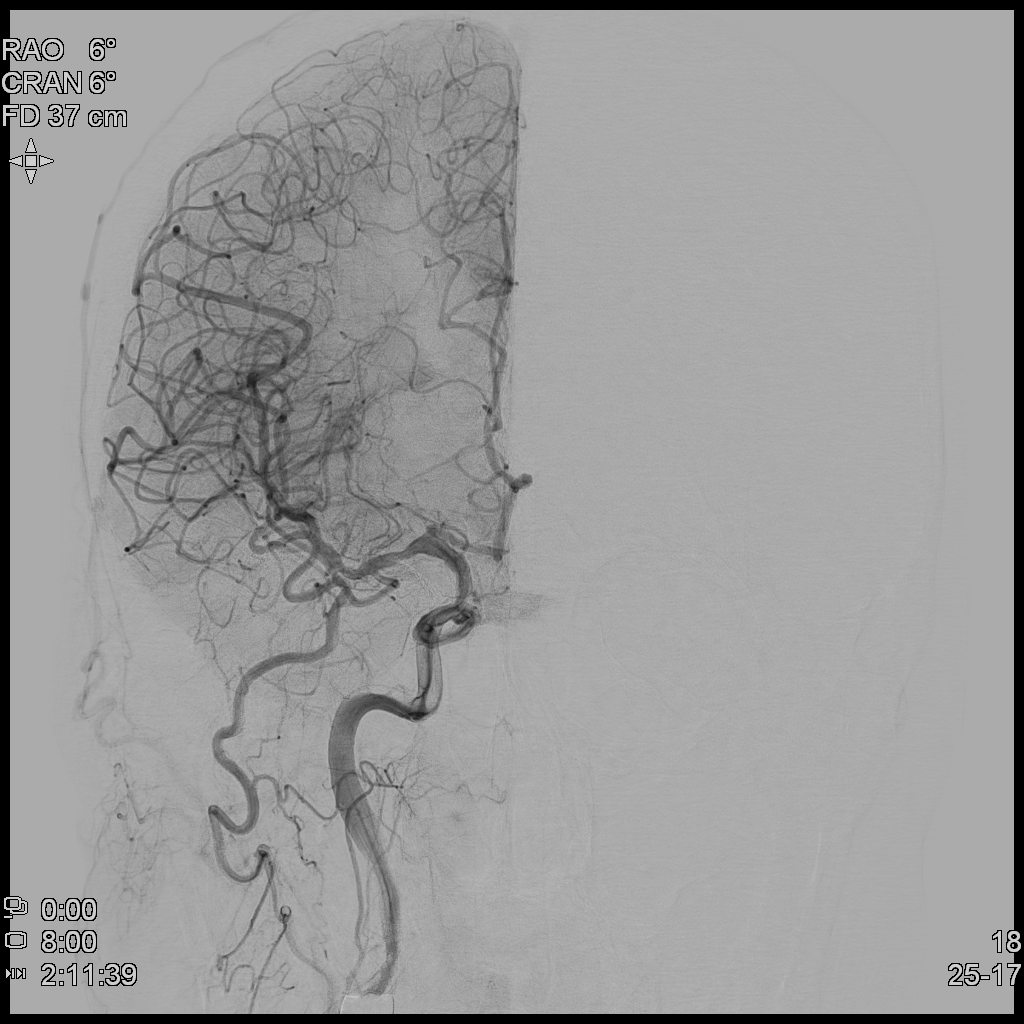

때문에 TFCA(Trans-Femoral Cerebral Angiography)를 통해 환자 뇌혈관의 막힌 혈관을 뚫어보고자 하였고, 환자는 1시간여만에 뇌혈관조영술을 시행하게 되었다.

뇌혈관조영술(TFCA)을 통해 어느정도 막힌 혈관의 일부를 뚫어내고 이후 혈류가 전달되는 모습을 확인하였다.